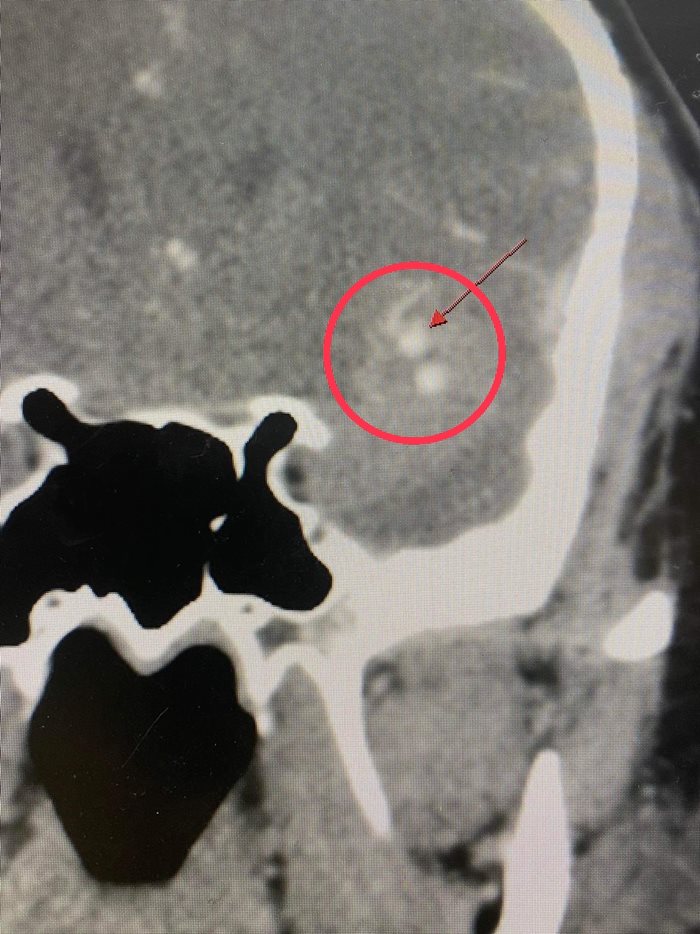

ผลเอกซเรย์น่าตกใจ คนไข้มีเส้นเลือดในสมองโป่งพอง ต้องผ่าตัดด่วน

จากภาพรังสี พบว่า คนไข้มีเส้นเลือดในสมองโป่งพอง เส้นเลือดปริแตก มีเลือดกระจายไปสู่เนื้อสมอง ขยายเป็นวง รอบเส้นเลือดที่แตก จึงปรึกษากับศัลยแพทย์ระบบประสาทและสมอง เพื่อเตรียมการผ่าตัดในทันที ก่อนที่เลือดออกในเนื้อสมองมากขึ้น จะส่งผลให้เนื้อสมองขาดเลือดเป็นวงกว้างไปมากกว่านี้